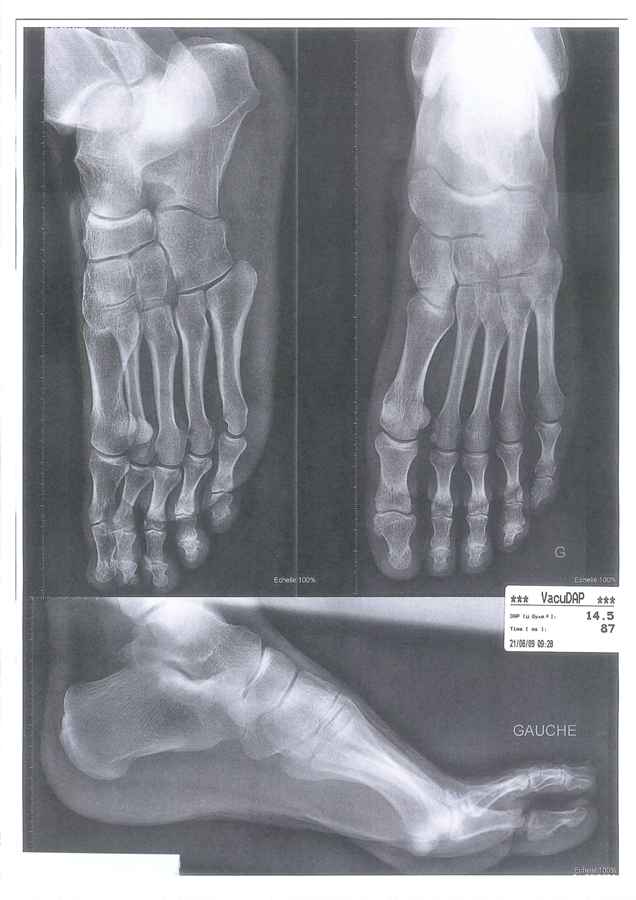

Après différents examens (radio et écho), il a été mis en évidence que la bosse au niveau de mon Scaphoïde gauche (voir photos) est dut à un échauffement du pied au contact de la zone d’ancrage de la bride supérieure. Cet échauffement se répète à chaque coupe de pied.